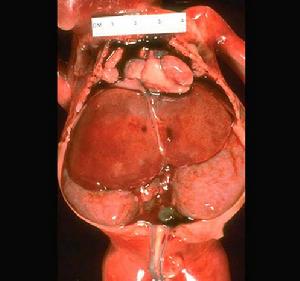

1.體格檢查,B超或CT發現腎囊腫。

2.尿路造影術顯示患腎有占位性病變,但CT或MRI除外囊腫惡變或腎癌液化。

3.囊腫巨大,有壓迫症狀或疑有惡變則宜手術治療。